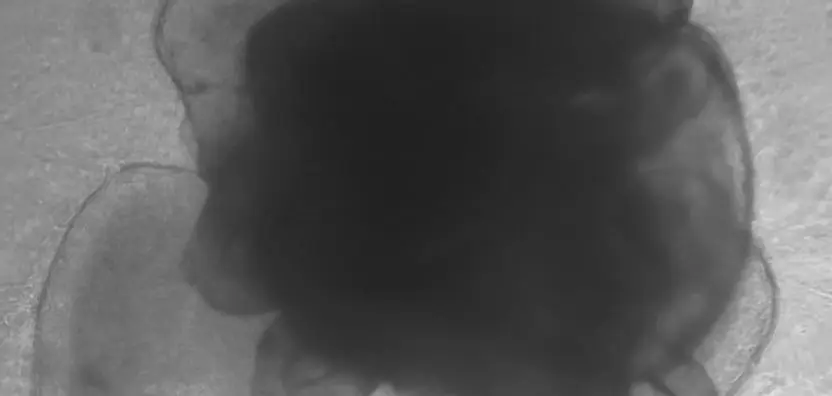

Our newly developed drug differs from previously known therapeutics in that it directly penetrates various tumor tissues to exert its efficacy. Therefore, it was essential to analyze the drug’s penetration within the tumor microenvironment. To evaluate this, we conducted permeability testing in a co-culture system of tumor organoids and cancer-associated fibroblasts (CAF). This approach allowed us to determine the optimal drug concentration required for effective therapeutic action. As a result,...

Pancreatic cancer is one of the most challenging malignancies to diagnose early, as it presents few or no symptoms in its initial stages. It is also known to have the lowest survival rate among all cancers. Additionally, the tumor microenvironment (TME) of pancreatic cancer poses significant barriers to drug penetration, driving the development of innovative therapeutic strategies to overcome these challenges. To better replicate the pancreatic cancer microenvironment, we conducted...